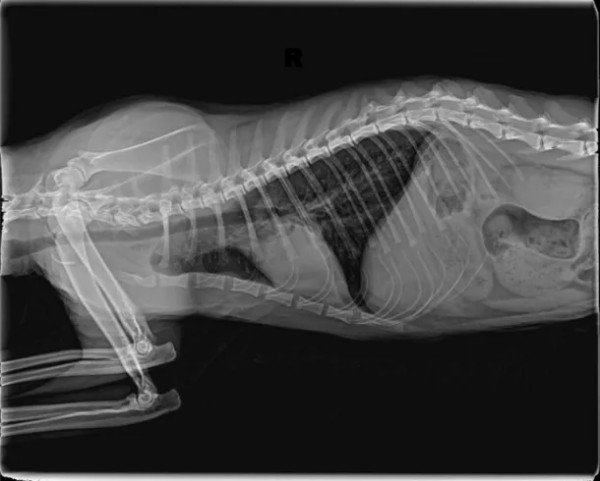

一、引言 猫咪肺炎根据发病快慢有急性肺炎和慢性肺炎之分,猫咪急性肺炎的症状主要表现为突然发高烧、呼吸不畅、腹泻等;慢性肺炎通常表现为长时间咳嗽、有痰、食欲下降、精神不振、呼吸不畅等。 猫咪如果患上肺炎就需要及时治疗,否则很容易引发相关的并发症,威胁到猫咪的性命。肺炎常见原因:感染性(细菌感染、病毒感染、寄生虫感染)、非感染性(吸入性、异物性、过敏性、继发性等) 二、病例基本信息及病史 2.1基本信息 一只缅因猫,雄性未绝育,体重5.85Kg,免疫不全,驱虫正常。 2.2主诉疾病史 最近几天精神良好,就诊当天发蔫,食欲不振,偶尔咳嗽,打喷嚏,4天前家里新领养一只小猫。既往病史 :疱疹病毒,杯状病毒,伯氏杆菌。 三、检查及化验项目和结果 3.1血常规检查 3.2 血清样淀粉蛋白检查 3.3生化检查 3.4fNT-PrOBNP猫N端脑钠肽前体 3.5影像学检查 四、诊断结果 肺炎;肺叶实变 五、治疗方案及预后 5.1经验性治疗 克维舒:一天两次,一次2ml; PO 麻杏石甘汤:一天两次,一5ml;PO 5.2复诊 用药2周后复诊,整体情况好转,咳嗽明显好转,喷嚏减少,分泌物减少,食欲恢复。炎症指标明显好转,肺部影像明显好转。 5.3复查结果 5.3.1血常规检查 5.3.2 血清样淀粉蛋白检查 5.3.3影像学检查 图4胸腔侧位 5.4治疗转归 巩固治疗:克维舒 一天两次,一次2ml,PO 该动物目前恢复良好,状态稳定,直至投稿前回访,一切正常。肺实变位置需密切监测,病变位置可能伴随终身。 六、讨论及小结 猫咪肺炎的发病原因一般是由细菌、真菌、病毒等微生物感染引起。甚至像寄生虫移行、外力因素、吸入性因素、机体免疫力下降等,都可诱发肺炎。严重的肺炎可能会导致肺部渗出增多、肺水肿等,引起急性呼吸困难。猫咪的肺炎在初期通常很隐蔽,甚至没有太大的症状和表现,发病非常突然,以精神沉郁、厌食、急性的呼吸困难为主,送医不及时容易耽误病情。该病例因为发现较早,治疗后整体预后良好。 肺炎的诊断:咳嗽的犬猫出现发烧、嗜睡、食欲不振或呼吸急促症状时应进行全面检查,血细胞计数和胸部X线检查评估是否存在肺炎。根据结果怀疑细菌性或支持细菌性肺炎的诊断时,应采集气管,支气管内或支气管肺泡灌洗进行细胞学检查,需氧培养、药敏实验和支原体培养。该病例未做相关检查,主人要求先对症治疗。 在开始抗菌治疗之前,都应该建议宠主进行培养和药敏实验,前提时动物状况足够稳定。但所有治疗检查应和宠主充分沟通,特别时需要长时间或管理时间比较长的病例,在治疗时应制定个性化治疗方案,将宠物主人的意愿,配合程度,可自由支配时间,动物配合程度都应纳入考量,从而提高治疗质量,护理质量以及医从性。 该病例综合考虑最终抗菌药物选用克维舒,一方面该病例未做培养及药敏,作为临床医生应选择一线广谱抗菌药物,安全性高的药物,从而提高治愈率。另一方面考虑到动物主人时间以及该猫吃药困难,克维舒易口服,操作简单,很大程度上减少猫咪应激,节省主人时间,同时增加了宠主成就感。从而提高了治愈率,也增加了宠主对医生的信任,所以最终选择了克维舒。 七、参考文献 1.Sykes, J. E. (2014).Feline lower respiratory tract disease. In J. E. Sykes (Ed.), Canine and Feline Infectious Diseases (pp. 161-173). 2.Reinero, C. R. (2011).Feline Asthma and Bronchopulmonary Disease. Veterinary Clinics of North America: Small Animal Practice, 41(2), 191–211. 3.Lappin, M. R., Blondeau, J., Boothe, D., Breitschwerdt, E. B., Guardabassi, L., Lloyd, D. H., ... & Sykes, J. E. (2017).Antimicrobial use Guidelines for Treatment of Respiratory Tract Disease in Dogs and Cats: Antimicrobial Guidelines Working Group of the International Society for Companion Animal Infectious Diseases. Journal of Veterinary Internal Medicine, 31(2), 279–294. 4.夏兆飞,陈艳云,王姜维主译.小动物内科学(第5版) [M].中国农业大学出版社,2019,11:297-300.